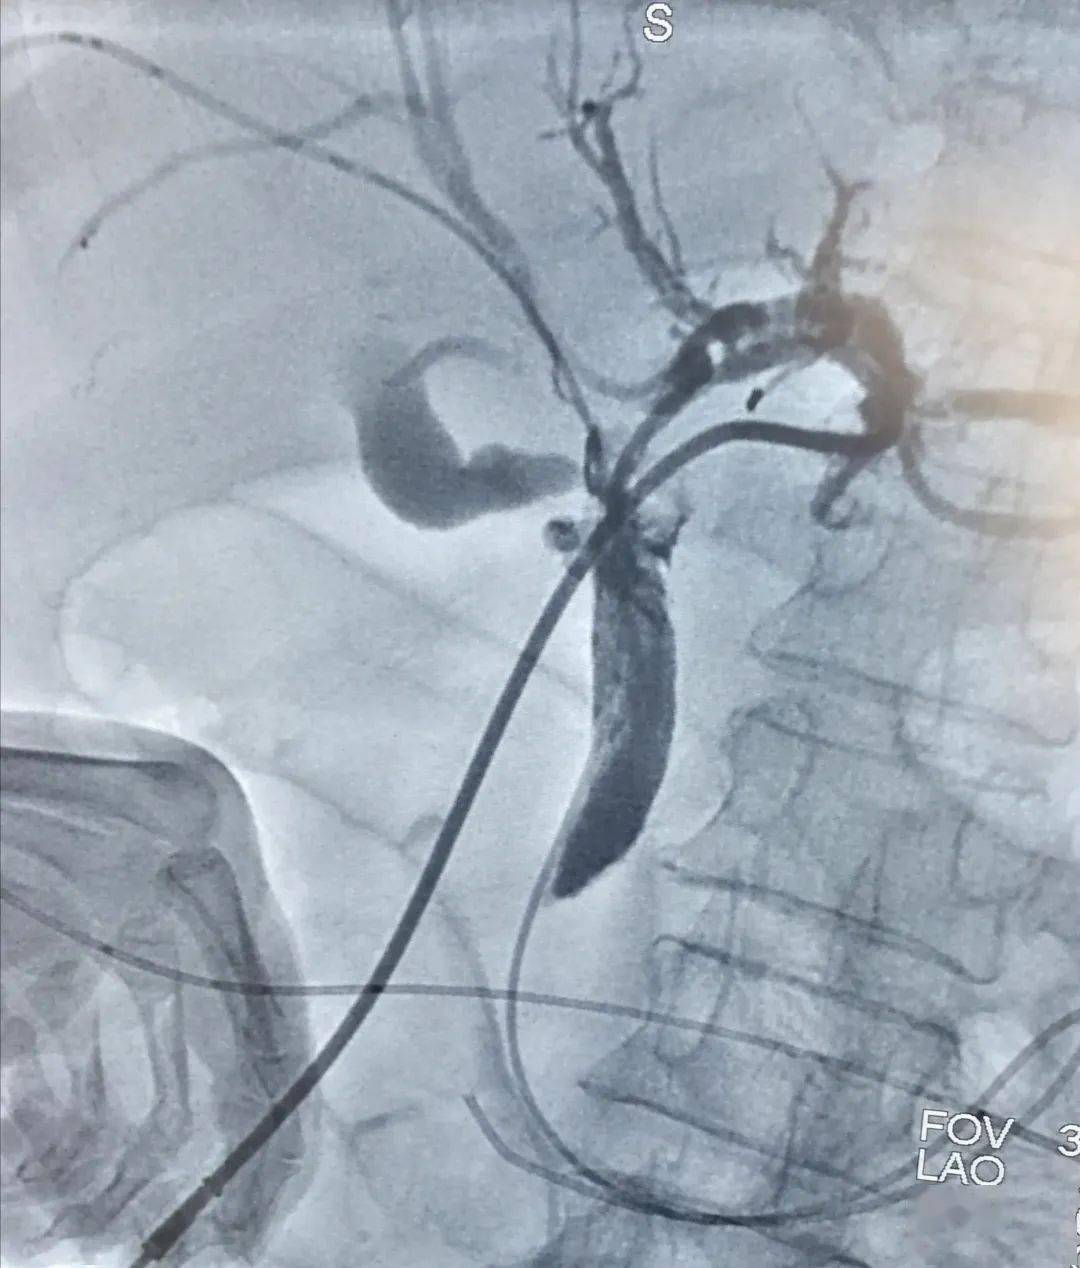

术前mri显示肿瘤及肝内胆管扩张(左) ptbd显示肝门区胆管侵犯

术后的片子,ptbd管每天引流量小于50ml.